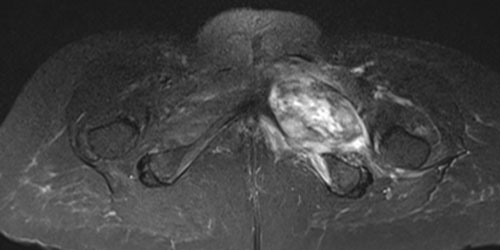

Chondrosarcoma is a malignant tumor of the bone that originates from cartilage tissue. Chondrosarcoma usually occurs after the age of 40 and is more common in men.